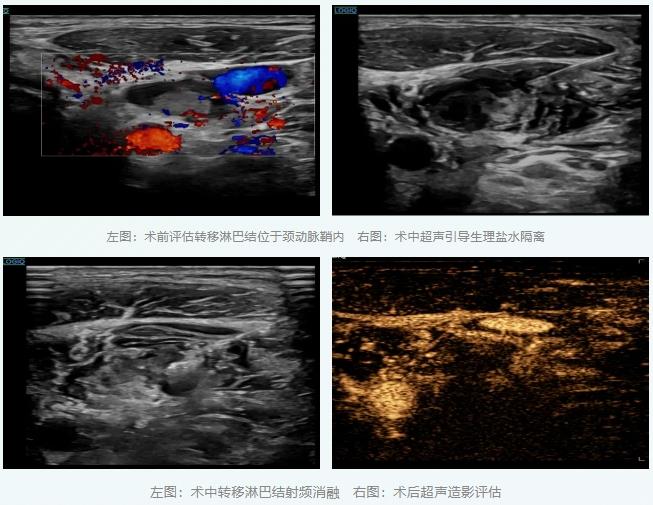

病例一:颈动脉旁的“精准拆除”

一位60多岁的男性患者,因甲状腺乳头状癌术后,发现颈部转移的淋巴结未被清扫,淋巴结位于左侧颈动脉鞘内,大小约21×13×12毫米,紧紧贴着颈内静脉、颈总动脉及迷走神经,像一颗“不定时炸弹”让患者时常惴惴不安,患者难以接受再次外科手术,且传统手术剥离风险极高,易导致大出血或神经损伤。

面对挑战,超声医学科李彦青主任团队制定了周密的方案。术中,在超声实时动态引导下,利用生理盐水隔离技术,巧妙地在转移淋巴结与周边重要的血管神经之间营造出一个安全的“操作空间”。随后,射频消融针精准抵达病灶,在完整灭活肿瘤的同时,完美保护了所有关键解剖结构。术后超声造影显示消融完全,患者当天出院。后续进一步内科治疗。